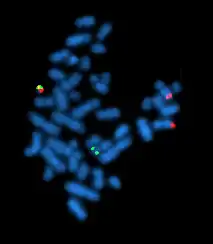

Fluorescent in situ hybridization

Fluorescent in situ hybridization (FISH) refers to using fluorescently labeled probe to hybridize to cytogenetic cell preparations.

Slide preparation

This section refers to preparation of standard cytogenetic preparations

The slide is aged using a salt solution usually consisting of 2X SSC (salt, sodium citrate). The slides are then dehydrated in ethanol, and the probe mixture is added. The sample DNA and the probe DNA are then co-denatured using a heated plate and allowed to re-anneal for at least 4 hours. The slides are then washed to remove excess unbound probe, and counterstained with 4',6-Diamidino-2-phenylindole (DAPI) or propidium iodide.

Analysis

Analysis of FISH specimens is done by fluorescence microscopy by a clinical laboratory specialist in cytogenetics. For oncology generally a large number of interphase cells are scored in order to rule out low-level residual disease, generally between 200 and 1,000 cells are counted and scored. For congenital problems usually 20 metaphase cells are scored.